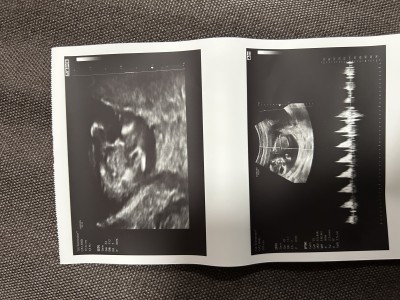

Ultrason kâğıdından anlayan var mı acaba rica etsem yorumlar mısınız

Gebelik haftası 13+6

Cinsiyeti erkek hayırlı olsun ben öyle gördüm

Erkek bebek. Hayırlısı olsun 💙